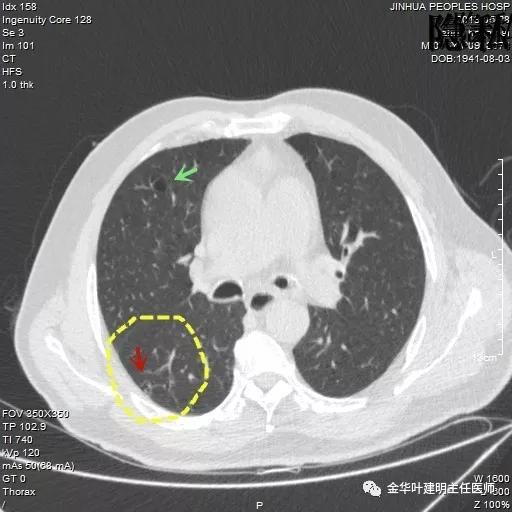

以上是2018年5月的片子,此处也呈空腔性病灶,但也点像是个肺大泡,因为绿色箭头所指处也有肺大泡。

如果我们把各个时候的片子放在一起对比,就会发现右下叶背段的空腔性病灶是从无到有,并逐渐进展的:

逐渐进展的空腔性病灶,特别边缘还是磨玻璃样的,需要特别当心,虽然有的层面看上去似肺大泡,但仍需我们提高警惕,注意必要的随访复查。